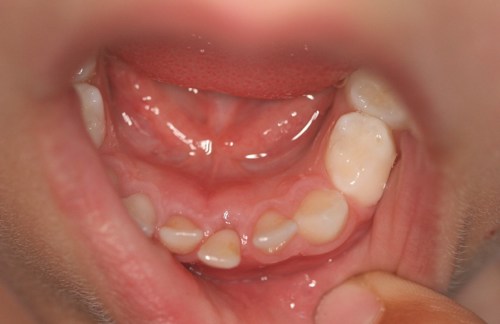

Det første billede ovenfor viser den første løse mælketand, der skal skiftes.

Der kan godt gå flere måneder, før den nye tand kommer til syne. Nogle gange bryder de nye tænder frem ved siden af mælketænderne. Hvis mælketænderne ikke vil falde ud af sig selv, kan man være nødt til, at trække den ud.

På første billede er den blivende fortand kommet skævt frem, og den har ikke skubbet mælketanden ud. På andet billede kommer de blivende fortænder fint frem.